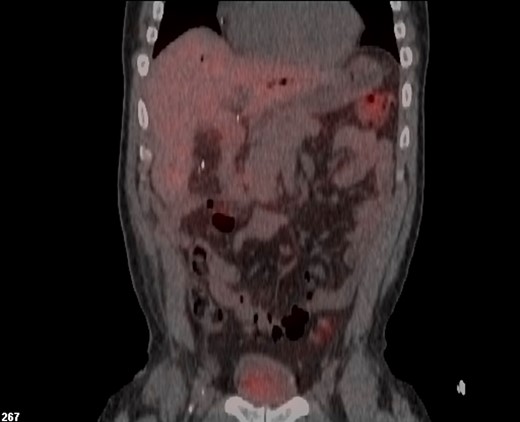

Final pathology demonstrated a well-differentiated NET, intermediate grade, infiltrating the entire length of the hepatic duct and common bile duct, ~4 cm in length. One of four periductal lymph nodes was also positive for metastatic NET, while the celiac, hepatic artery and portal lymph nodes were negative for tumor. The pathological stage was pT2,N1. Ki-67 immunostaining revealed a proliferative index of 4%. Given the unexpected final pathology, an octreotide scan was performed postoperatively showing no evidence of hepatic or extrahepatic disease, and chromogranin A and serotonin were within normal limits (Fig. 3). Follow-up MRI at 6 months post-op showed no evidence of recurrent or residual disease, and the patient is currently asymptomatic and doing well. The unexpected pathology was discussed in our interdisciplinary liver tumor board. No further adjuvant therapy, such as somatostatin, was recommended given the completely resected tumor and lack of symptoms with normal serotonin and chromogranin A levels and absence of extrahepatic disease.

Postoperative In-111 octreotide scan showing no evidence of persistent or recurrent disease following biliary resection and hepaticojejunostomy reconstruction.